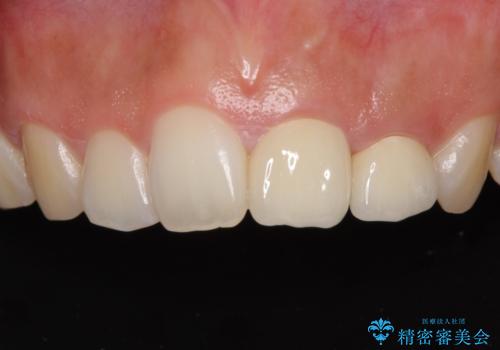

上顎のむし歯の酷い残存乳歯は抜歯をし、矯正治療の途中でインプラントを埋入、矯正治療後に補綴治療を行うこととしました。

セラミック治療の注意事項(リスク・副作用など)

- 天然歯を削ります

- 硬い素材は天然歯を傷つけてしまう場合があります

- かみ合わせや歯ぎしりが強すぎる方はセラミックが割れてしまう可能性があります